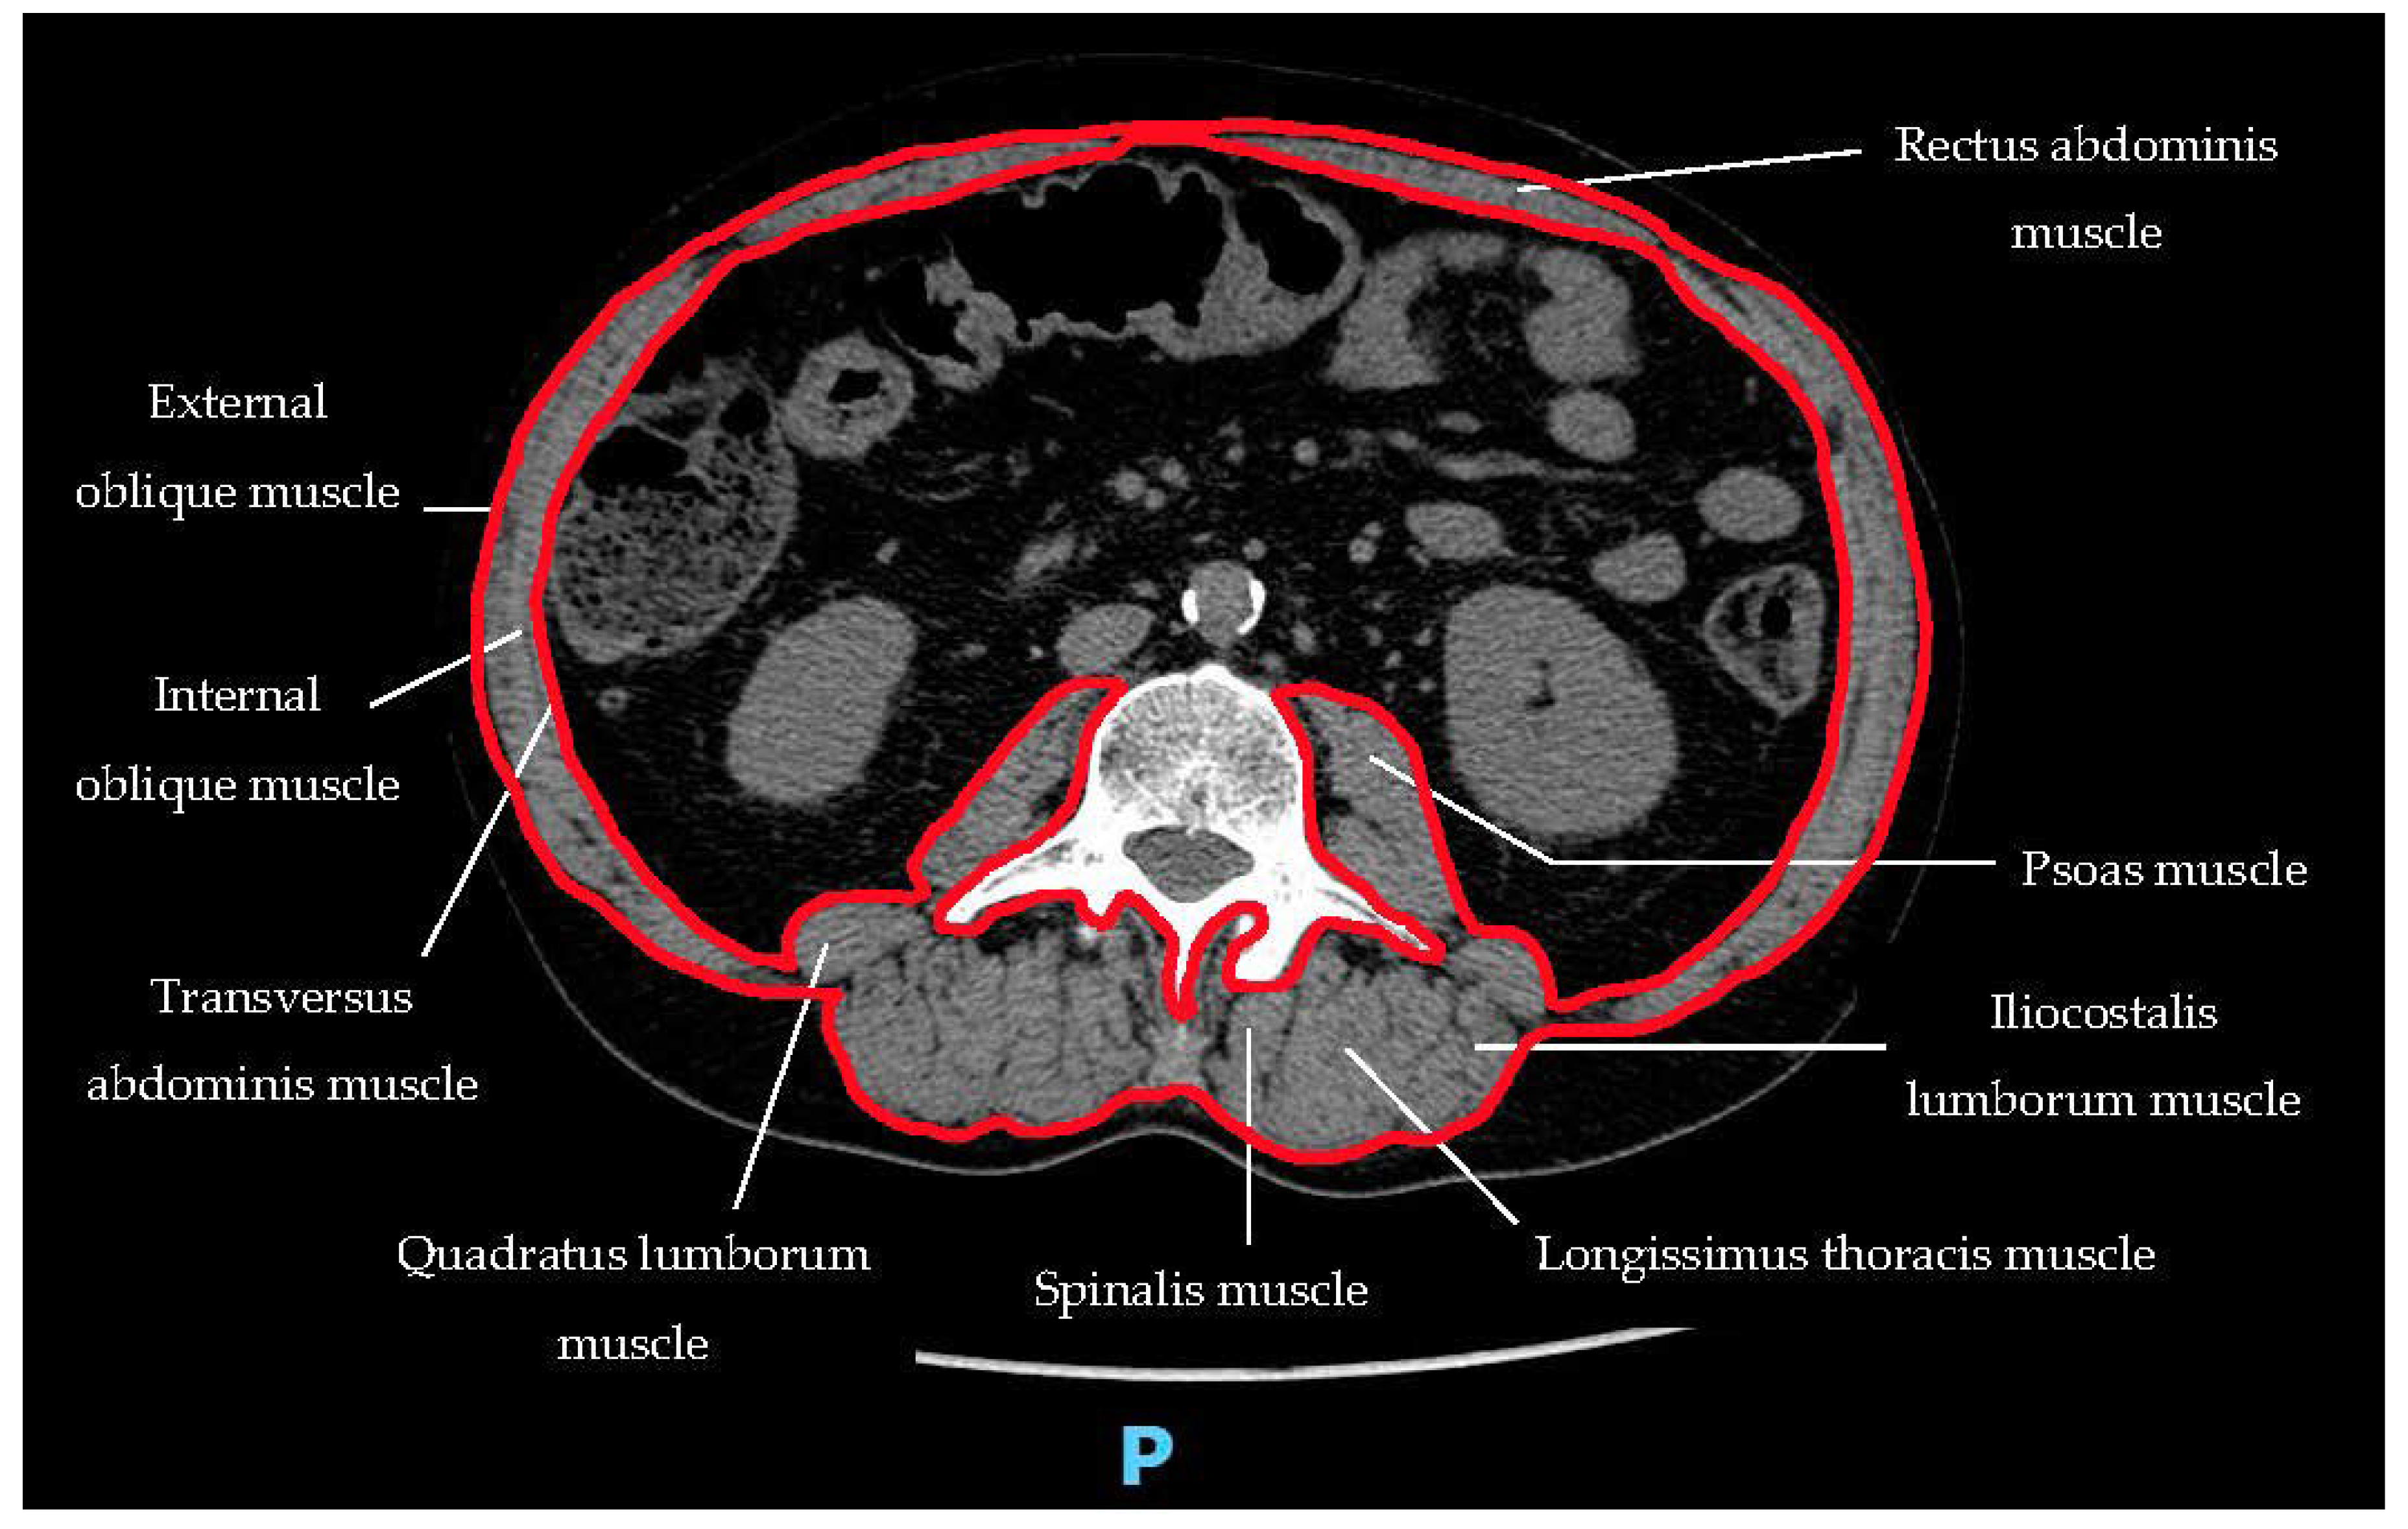

| Skeletal muscle mass or skeletal muscle quality | Appendicular skeletal muscle mass by Dual-energy X-ray absorptiometry [46]; Whole-body skeletal muscle mass or appendicular skeletal muscle mass predicted by Bioelectrical impedance analysis [47]; Lumbar muscle cross-sectional area by CT or MRI [48,49] |